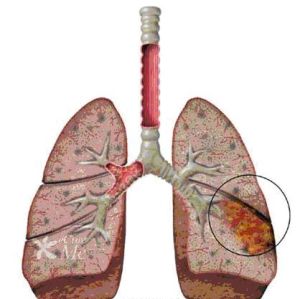

肺孢子蟲屬低致病力、生長繁殖緩慢的寄生性原蟲,健康宿主有抵禦能力只形成隱性感染。細胞免疫受損是宿主最主要的易患因素,如嬰幼兒營養不良,先天性免疫缺陷兒童,惡性腫瘤、器官移植或接受免疫抑制治療及AIDS患者。在AIDS病人中的發病高達80%~90%。當T細胞免疫功能抑制時,寄生於肺泡的肺孢子蟲可大量繁殖,對上皮細胞造成直接的毒素性損害,引起I型上皮脫屑性肺泡炎。肺泡間隔有漿細胞,單核細胞浸潤,肺泡上皮增生,增厚,泡腔內充滿嗜酸性泡沫樣物質和蛋白樣滲出物。嚴重病例有廣泛間質和肺泡性水腫。肺泡腔內充滿炎性細胞,蛋白樣滲出物和蟲體,阻礙氣體交換,產生臨床症狀。

PCP病毒性肺炎其臨床特點為發熱、乾咳、呼吸困難、鼻翼煽動和紫紺等,症狀進行性加重,單純吸氧不能緩解,經特效治療後可迅速恢復。隨著惡性腫瘤化療的普及、臟器移植和自身免疫抑制劑的增多,PCP的發病有所增加。PCP也是AIDS病最常見的感染併發症和最主要的死亡原因之一。PCP好發於免疫缺陷的兒童和成年人,偶發生於健康人。本病的主要臨床特點為大多數病人有發熱、呼吸困難和紫紺及乾咳等,僅根據臨床表現不易診斷。PCP胸片的典型改變為雙側瀰漫性肺泡和間質浸潤,開始由肺門向外擴展,隨之迅速實變為蝶狀陰影,肺尖和肺底很少累及。